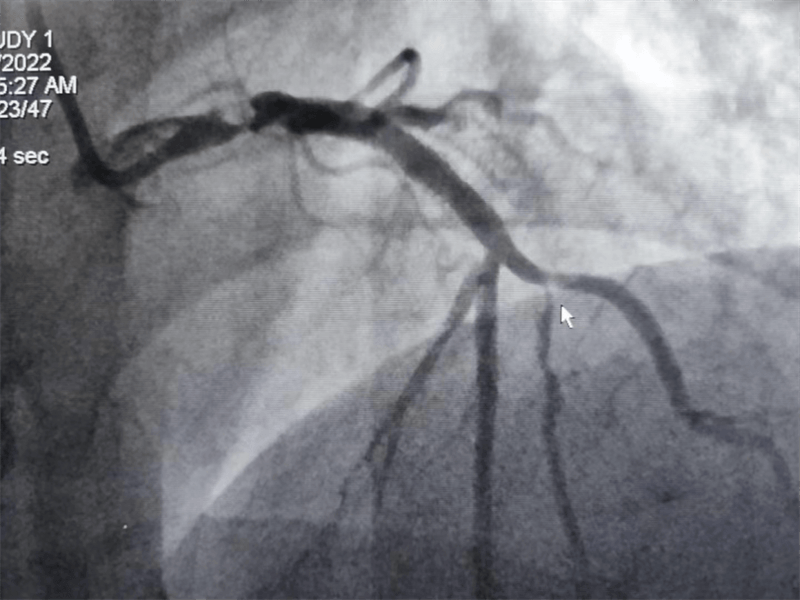

冠脈造影結(jié)果提示:左主干末端及前降支開(kāi)口處99%狹窄,回旋支開(kāi)口處80-90%狹窄,中段支架內(nèi)100%閉塞??吹皆煊敖Y(jié)果時(shí),在場(chǎng)醫(yī)護(hù)人員無(wú)不驚出一身冷汗:左主干病變“細(xì)”如發(fā)絲——生死一線牽!患者拒絕搭橋手術(shù),所以選擇介入處理該病變。

患者在冠脈造影檢查術(shù)中,感到胸悶、胸痛發(fā)作,血壓下降、心率減慢,我們立即對(duì)左主干狹窄段進(jìn)行球囊擴(kuò)張后癥狀好轉(zhuǎn),生命體征逐漸平穩(wěn)。

我們結(jié)合患者病變特點(diǎn),對(duì)回旋支支架內(nèi)閉塞病變處藥物球囊治療,左主干病變植入1枚支架,術(shù)后,造影顯示左主干病變處支架植入狀態(tài)良好,血管內(nèi)超聲顯示支架貼壁良好,患者血壓、心率穩(wěn)定,癥狀完全緩解,并安全返回重癥監(jiān)護(hù)室進(jìn)一步治療,術(shù)后張大伯無(wú)明顯不適,生命體征穩(wěn)定,病情明顯好轉(zhuǎn)。